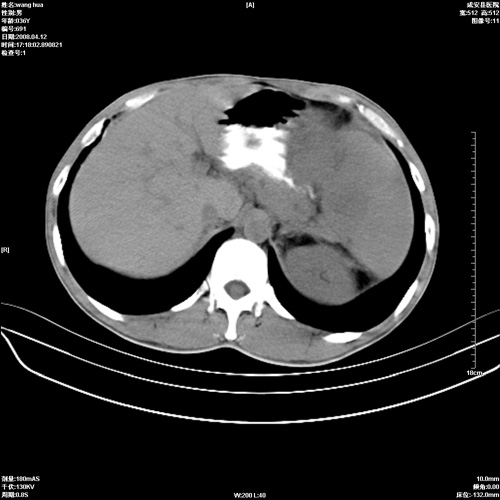

标题: CT12809:男36岁,自感上腹胀5天,B超诊断为脾肾之间占位,血 [打印本页]

标题: CT12809:男36岁,自感上腹胀5天,B超诊断为脾肾之间占位,血

请各位老师先分析一下定位 明天做增强

确实需要强化!先大胆预测一下,来源于脾脏的占位,血管瘤或淋巴瘤可能性大。

脾脏肿瘤,有钙化,增强再说

脾脏明显增大,其内见巨大低密度灶,境界不清,病史较短,考虑恶性病变脾血管内皮细胞肉瘤可能。建议增强扫描与脾脏淋巴瘤及血管瘤鉴别。